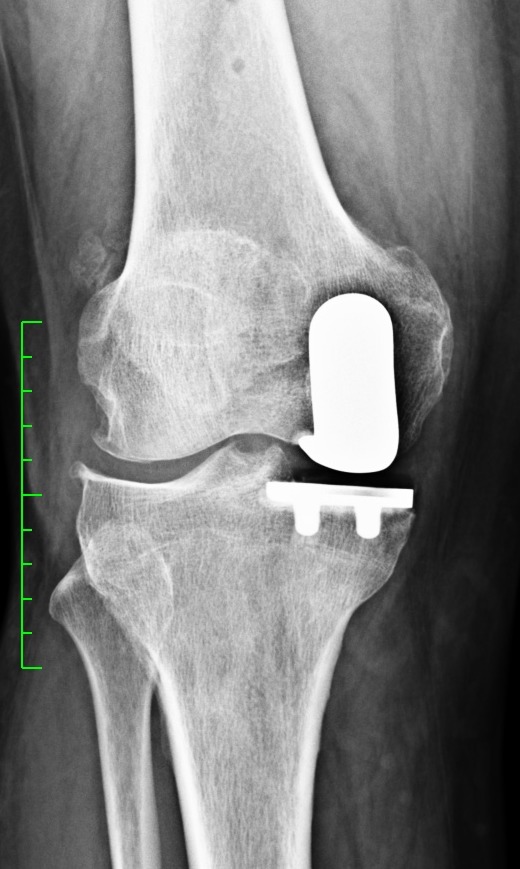

Con l’artrosi non sempre è necessaria la protesi totale di ginocchio. Nelle fasi iniziali, infatti, possono essere efficaci altri trattamenti conservativi infiltrazioni, fisioterapia e medicina rigenerativa. Tuttavia, quando anche questi trattamenti non hanno più beneficio per il paziente, è preferibile valutare anche l’opzione della chirurgia robotica per l’impianto della protesi.

L’estrema precisione data dalla tecnologia robotica applicata all’ortopedia protesica di ginocchio permette di ridurre drasticamente le cause principali di dolore anche a distanza dall’intervento, dovute a errori anche minimi di posizionamento della protesi. Poter tornare a camminare, fare le scale e muoversi senza dolore alle ginocchia è l’obiettivo, dopo l’intervento, per molte persone che soffrono di artrosi del ginocchio; per i più attivi e ai giovani, però, che richiedono anche di tornare a fare sport, la chirurgia robotica rappresenta la tecnologia più avanzata oggi a disposizione per poter recuperare il massimo movimento naturale nel più rapido tempo attualmente possibile.

“La chirurgia robotica è la più avanzata tecnologia oggi disponibile per la protesica di ginocchio. Il robot, in sostanza, sfrutta le immagini Tac del paziente per creare un modello 3D dell’arto su cui intervenire e su cui il chirurgo può eseguire una simulazione avanzata dell’intervento, dei risultati e degli eventuali rischi. In tal modo, il medico sa sempre anticipatamente qual è la taglia di protesi più adatta per ciascun paziente e il suo corretto posizionamento già prima di entrare in sala operatoria. La precisione del braccio robotico guidato dal chirurgo, consente di operare senza intaccare i tessuti sani circostanti.

Si, durante l’intervento, la tecnologia robotica usa uno speciale sistema di navigazione guidato da sensori posizionati in particolari punti della gamba del paziente che si interfacciano con il software del robot e permettono al chirurgo di eseguire in maniera estremamente precisa le azioni chirurgiche programmate, di valutare l’anatomia e la cinematica (il movimento) dell’arto del paziente. Ci aiuta a stabilire con precisione millimetrica l’inserimento del le componenti della protesi scelta. Inoltre con il braccio robotico, nella mano del chirurgo, si asporta solo la porzione di osso minima necessaria (quella danneggiata, usurata) al posizionamento definitivo della protesi, senza sacrificare più osso del necessario e proprio grazie a questo e tenendo conto della struttura muscolare e della tenuta dei legamenti, e anche delle richieste funzionali di ciascun paziente, che sono aspetti fondamentali dell’intervento perchè permette al paziente, dopo l’intervento, di non avvertire la sensazione di corpo estraneo all’interno del ginocchio, e di avere un recupero più rapido con minor dolore.